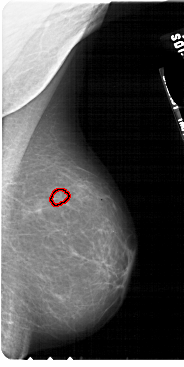

A_1891_1.RIGHT_CC

RIGHT_CC LINES 4981 PIXELS_PER_LINE 2716 BITS_PER_PIXEL 12 RESOLUTION 43.5 OVERLAY

FILE: A_1891_1.RIGHT_CC.OVERLAY

TOTAL_ABNORMALITIES 1

ABNORMALITY 1

LESION_TYPE CALCIFICATION TYPE PLEOMORPHIC DISTRIBUTION CLUSTERED

ASSESSMENT 4

SUBTLETY 2

PATHOLOGY BENIGN

TOTAL_OUTLINES 1

BOUNDARY